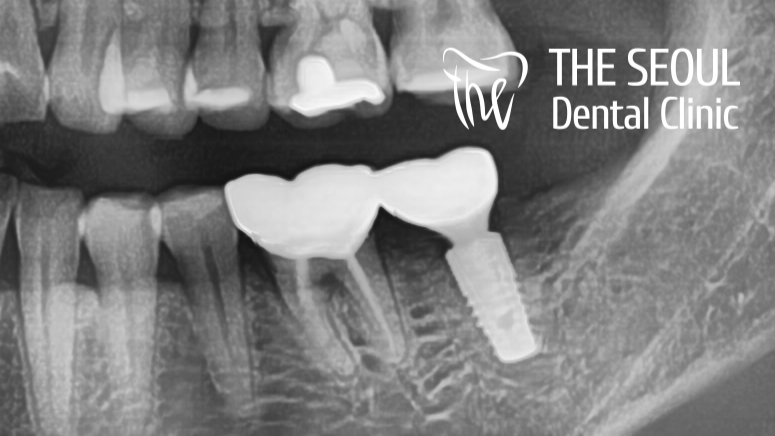

『위화감 없이 잘 어우러지고 있죠?』

크기는 물론이며 색조, 형태 모든 것에서

계획했던 대로 원하는 결과를 얻을 수 있었습니다.

기존에 치료받았던 곳, 남은 자연치들과

새롭게 올려드릴 크라운이

조화롭게 잘 어우러질 수 있도록

색조 선택부터 신중하게 진행을 했습니다.

크라운의 외형을 제작할 때도

어떻게 만들면 최대 효율을 낼지,

환자의 교합이 더 편할지

꼼꼼하게 확인을 한 뒤에 만들었는데요.